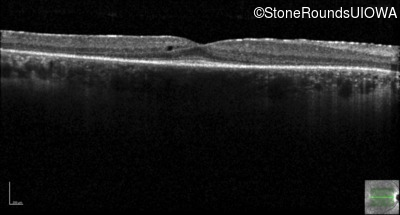

Optical Coherence Tomography - Right -

20/20 -1

Exemplar / OCT Stack